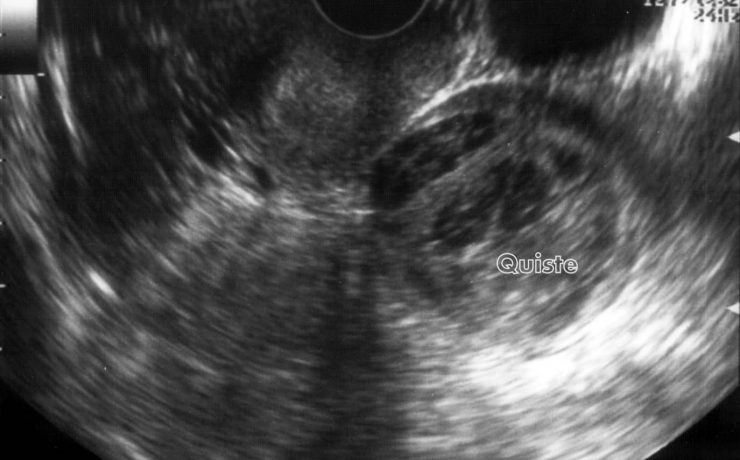

Mastitis granulomatosa idiopática

La mastitis granulomatosa idiopática es un proceso inflamatorio mamario benigno, poco frecuente, de origen desconocido. Se presenta en mujeres en edad reproductiva, entre los 17 y 42 años de edad. El diagnóstico se realiza por exclusión; para ello se utiliza ultrasonido, biopsia por aspiración de aguja fi na o biopsia